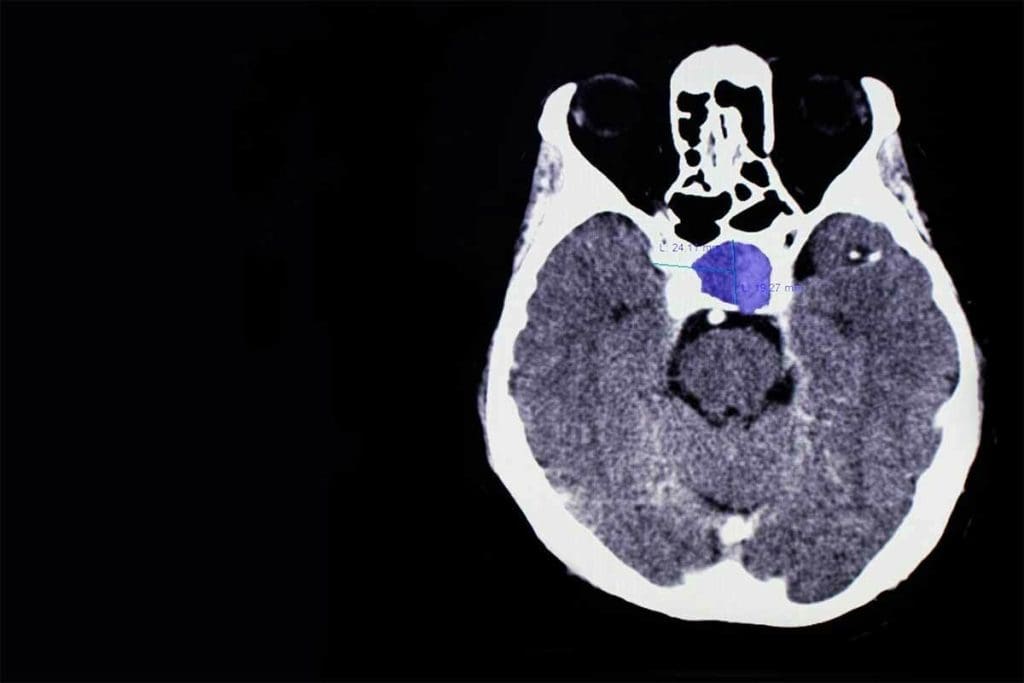

CT Thyroid Gland: 7 Essential Insights Revealed Now

CT Thyroid Gland: 7 Essential Insights Revealed Now 5

CT thyroid gland imaging is key in diagnosing and managing thyroid issues. It gives us detailed images of the thyroid gland. This helps us spot and track different thyroid problems.

What is a CT Scan of the Thyroid Gland?

A CT scan of the thyroid gland is a non-invasive test. It uses X-rays and computer tech to show detailed images of the thyroid and nearby areas. It’s great for checking the thyroid’s size, shape, and position, and for finding any oddities like nodules or tumors.